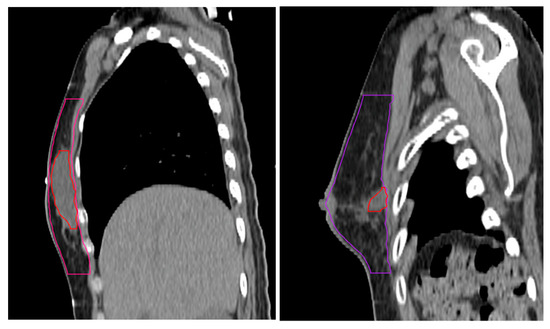

The dimensions of the surgical specimen, including width (cm), depth (cm), and height (cm), as well as the width and depth (cm) of the excised skin, were obtained from the gross pathology report. Skin depth and width were measured from the surgical pathology specimen. Skin depth was defined as the vertical thickness from the epidermis to the dermis and skin width as the lateral dimension of the excised skin. Measurements were taken from a representative area of the specimen using standardized calipers. The specimen volume (cc) was calculated by multiplying the width, depth, and height of the surgical specimen. Breast volume (cc) and surgical cavity (cc) were calculated by segmenting each axial slice of simulation computed tomography (CT) according to the RTOG guidelines [15] using MIM (MIM Software Inc., Cleveland, OH, USA). Surgical cavity was defined as a localized fluid attenuation, separate from the surrounding breast parenchyma on a CT image (Figure 1).

Figure 1. Segmentation of surgical cavity shown in axial (left) and sagittal (right) views of simulation CT.